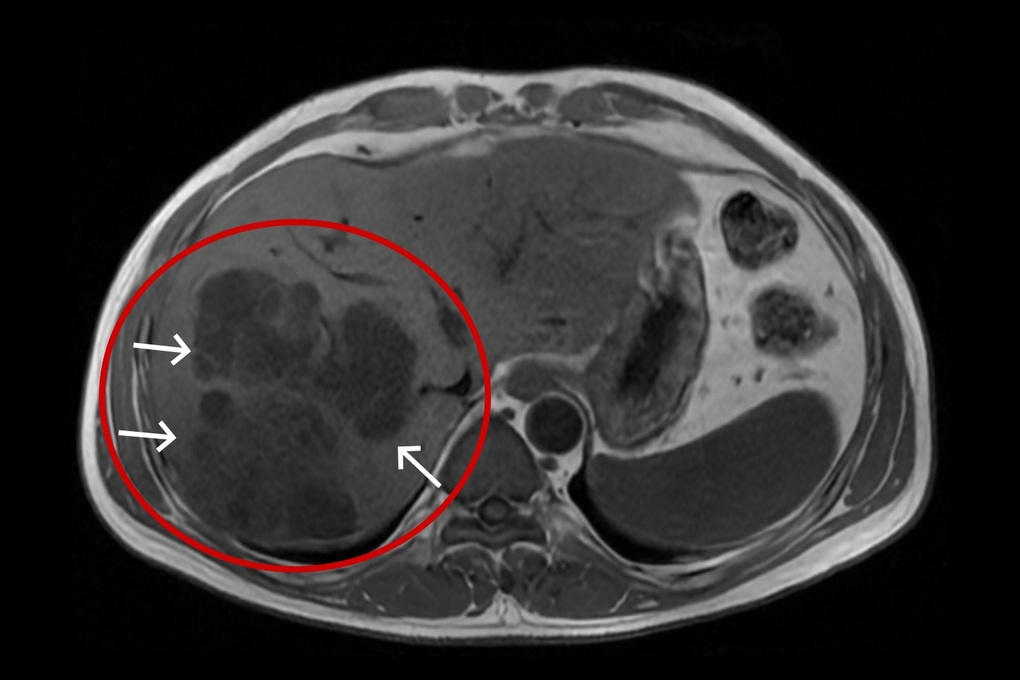

Đồng thời, kết quả siêu âm và chụp MRI ổ bụng cho thấy, nhu mô gan phải vùng hạ phân thùy VII – VIII xuất hiện một ổ tổn thương áp xe kích thước lớn 109 x 102 x 74mm, kèm theo nhiều ổ nhỏ xung quanh. Đáng lo ngại, đây không phải một ổ mủ đơn thuần mà có cấu trúc phức tạp, chứa nhiều vách ngăn, vỏ dày, tạo thành các chùm nang nằm sát vỏ gan, tiềm ẩn nguy cơ vỡ vào ổ bụng.

Chùm áp xe gan đa ổ kích thước lớn với nhiều vách ngăn (Ảnh: BVCC).